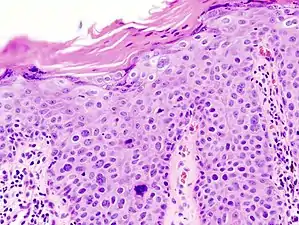

In situ disease

Bowen's disease is essentially equivalent to and used interchangeably with cSCC in situ, when not having invaded through the basement membrane.[12] Depending on source, it is classified as precancerous[13] or cSCC in situ (technically cancerous but non-invasive).[46][47] In cSCC in situ (Bowen's disease), atypical squamous cells proliferate through the whole thickness of the epidermis.[12] The entire tumor is confined to the epidermis and does not invade into the dermis.[12] The cells are often highly atypical under the microscope, and may in fact look more unusual than the cells of some invasive squamous-cell carcinomas.[12]

cSCC in situ, high magnification, demonstrating an intact basement membrane.[12]